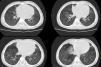

Due to suspicion of chronic aspiration syndrome secondary to dysphagia possibly associated with gastro-oesophageal reflux (the latter subsequently ruled out by pH-metry), a CT scan of the lungs was performed that revealed subsegmental atelectasis in the middle lobe and lingula with small areas of bronchiectasis and mild peribronchovascular thickening predominantly involving the lower lobes (Fig. 1). These findings motivated performance of flexible bronchoscopy, which evinced an abundance of mucus throughout the bronchial tree, and with collection of a bronchoalveolar lavage sample that was positive for Haemophilus influenzae. The treatment consisted of inhaled and nasal budesonide, nebulised hypertonic saline solution, respiratory physical therapy and oral azithromycin 3 days a week.